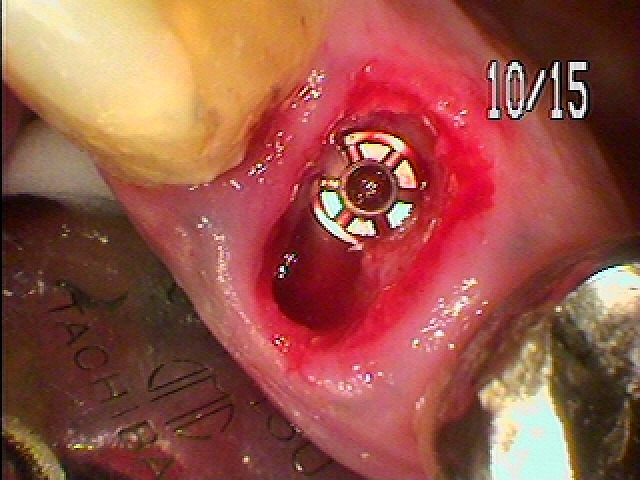

抜歯即時インプラント埋入を行っていきました